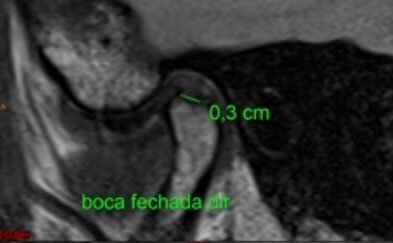

A Patologia Oral e Maxilofacial é a especialidade responsável pelo diagnóstico e tratamento de doenças que afetam a boca, mandíbula e estruturas faciais. Atua na identificação de lesões, cistos e tumores, garantindo diagnóstico preciso e tratamento adequado para preservar a saúde bucal e geral do paciente.